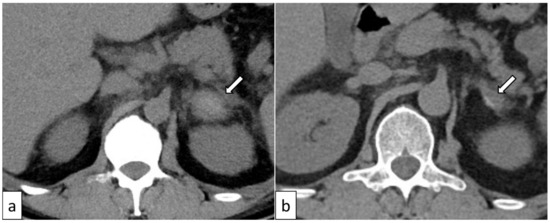

| Our case | 38 (Figure 2) | Male | YES | Ischemia/infarction | Bilateral | YES | YES | YES | YES |

3.4. Adrenal Ischemia/Infarction